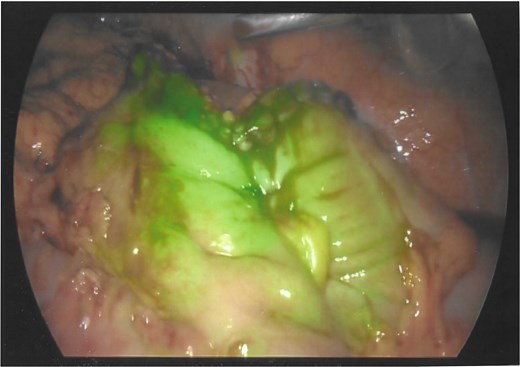

As a result, a laparoscopic left hemicolectomy was performed. The descending colon was medialised by incising the White line of Toldt from the proximal sigmoid colon, with dissection of splenocolic, phrenicocolic and the pancreaticocolic ligaments proximally. The colocutaneous fistula was identified during medialisation of the proximal descending colon and was excised (Fig. 1). There were chronic changes of inflammation and fibrosis around this region, without an abscess cavity. The distal transverse colon was then mobilised by dissecting the gastrocolic ligament to enter the lesser sac. The mobilised colon was then exteriorised through a midline laparotomy, the left colic and the left branch of the middle colic arteries were ligated and an extracorporeal side to side, functional end to end stapled anastomosis occurred using NTLC 75 mm blue reload stapler between the distal transverse and the distal descending colon. Indocyanide Green (ICG) angiography was used to confirm good perfusion at the anastomosis (Fig. 2). A well vascularised omental patch covered the remnant fistula tract on the lateral posterior abdominal wall. Postoperative recovery was uncomplicated. Histopathology was consistent with a fistula tract without evidence of malignancy.

Laparoscopic view of the excised colocutaneous fistula (arrow). The descending colon has been retracted medially.